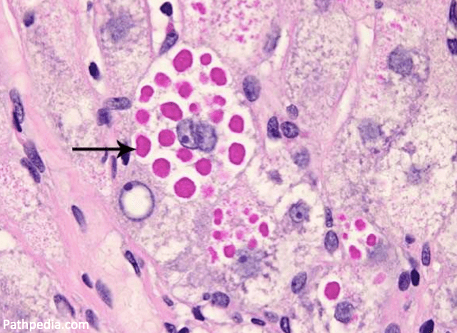

Histologically, liver sections from alpha-1 antitrypsin deficiency patients show PAS-positive inclusions or clumps filling the tissue. These clumps are polymerized alpha-1 antitrypsin aggregating in hepatocytes. This accumulation is called a toxic gain of function,” as opposed to the toxic loss of function that leads to emphysema.

The ZZ genotype provides the best example, as it is the most common mutation in alpha-1 antitrypsin deficiency and has the strongest association with liver disease. In those with the ZZ genotype, there is a crucial amino acid substitution where a lysine is substituted for glutamic acid in a specific hinge point in the structure of the protein. This disrupted hinge point causes protein misfolding, polymerization of the misfolded protein, and accumulation of the abnormal alpha-1 in the endoplasmic reticulum of hepatocytes. These inclusions cause mitochondrial damage leading the injured mitochondria to release reactive oxygen species resulting in hepatocyte damage. This process has been called proteotoxic stress.